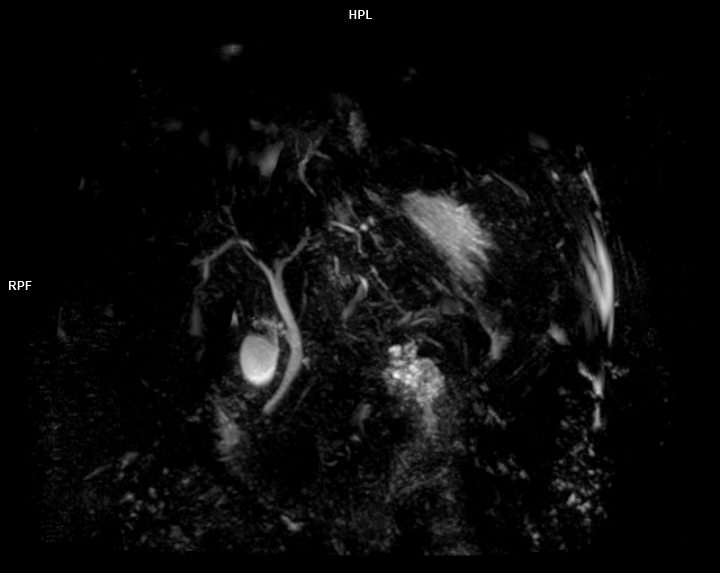

3 Tesla MR Çekim Görüntüleri

• 3 Tesla MR Çekim Görüntüleri